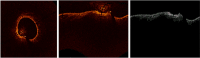

Kawasaki disease (KD) is an acute childhood disease complicated by coronary artery aneurysms, intima thickening, thrombi, stenosis, lamellar calcifications, and disappearance of the media border. Automatic classification of the coronary artery layers (intima, media, and scar features) is important for analyzing optical coherence tomography (OCT) images recorded in pediatric patients. OCT has been known as an intracoronary imaging modality using near-infrared light which has recently been used to image the inner coronary artery tissues of pediatric patients, providing high spatial resolution (ranging from 10 to 20 μm). This study aims to develop a robust and fully automated tissue classification method by using the convolutional neural networks (CNNs) as feature extractor and comparing the predictions of three state-of-the-art classifiers, CNN, random forest (RF), and support vector machine (SVM). The results show the robustness of CNN as the feature extractor and random forest as the classifier with classification rate up to 96%, especially to characterize the second layer of coronary arteries (media), which is a very thin layer and it is challenging to be recognized and specified from other tissues.